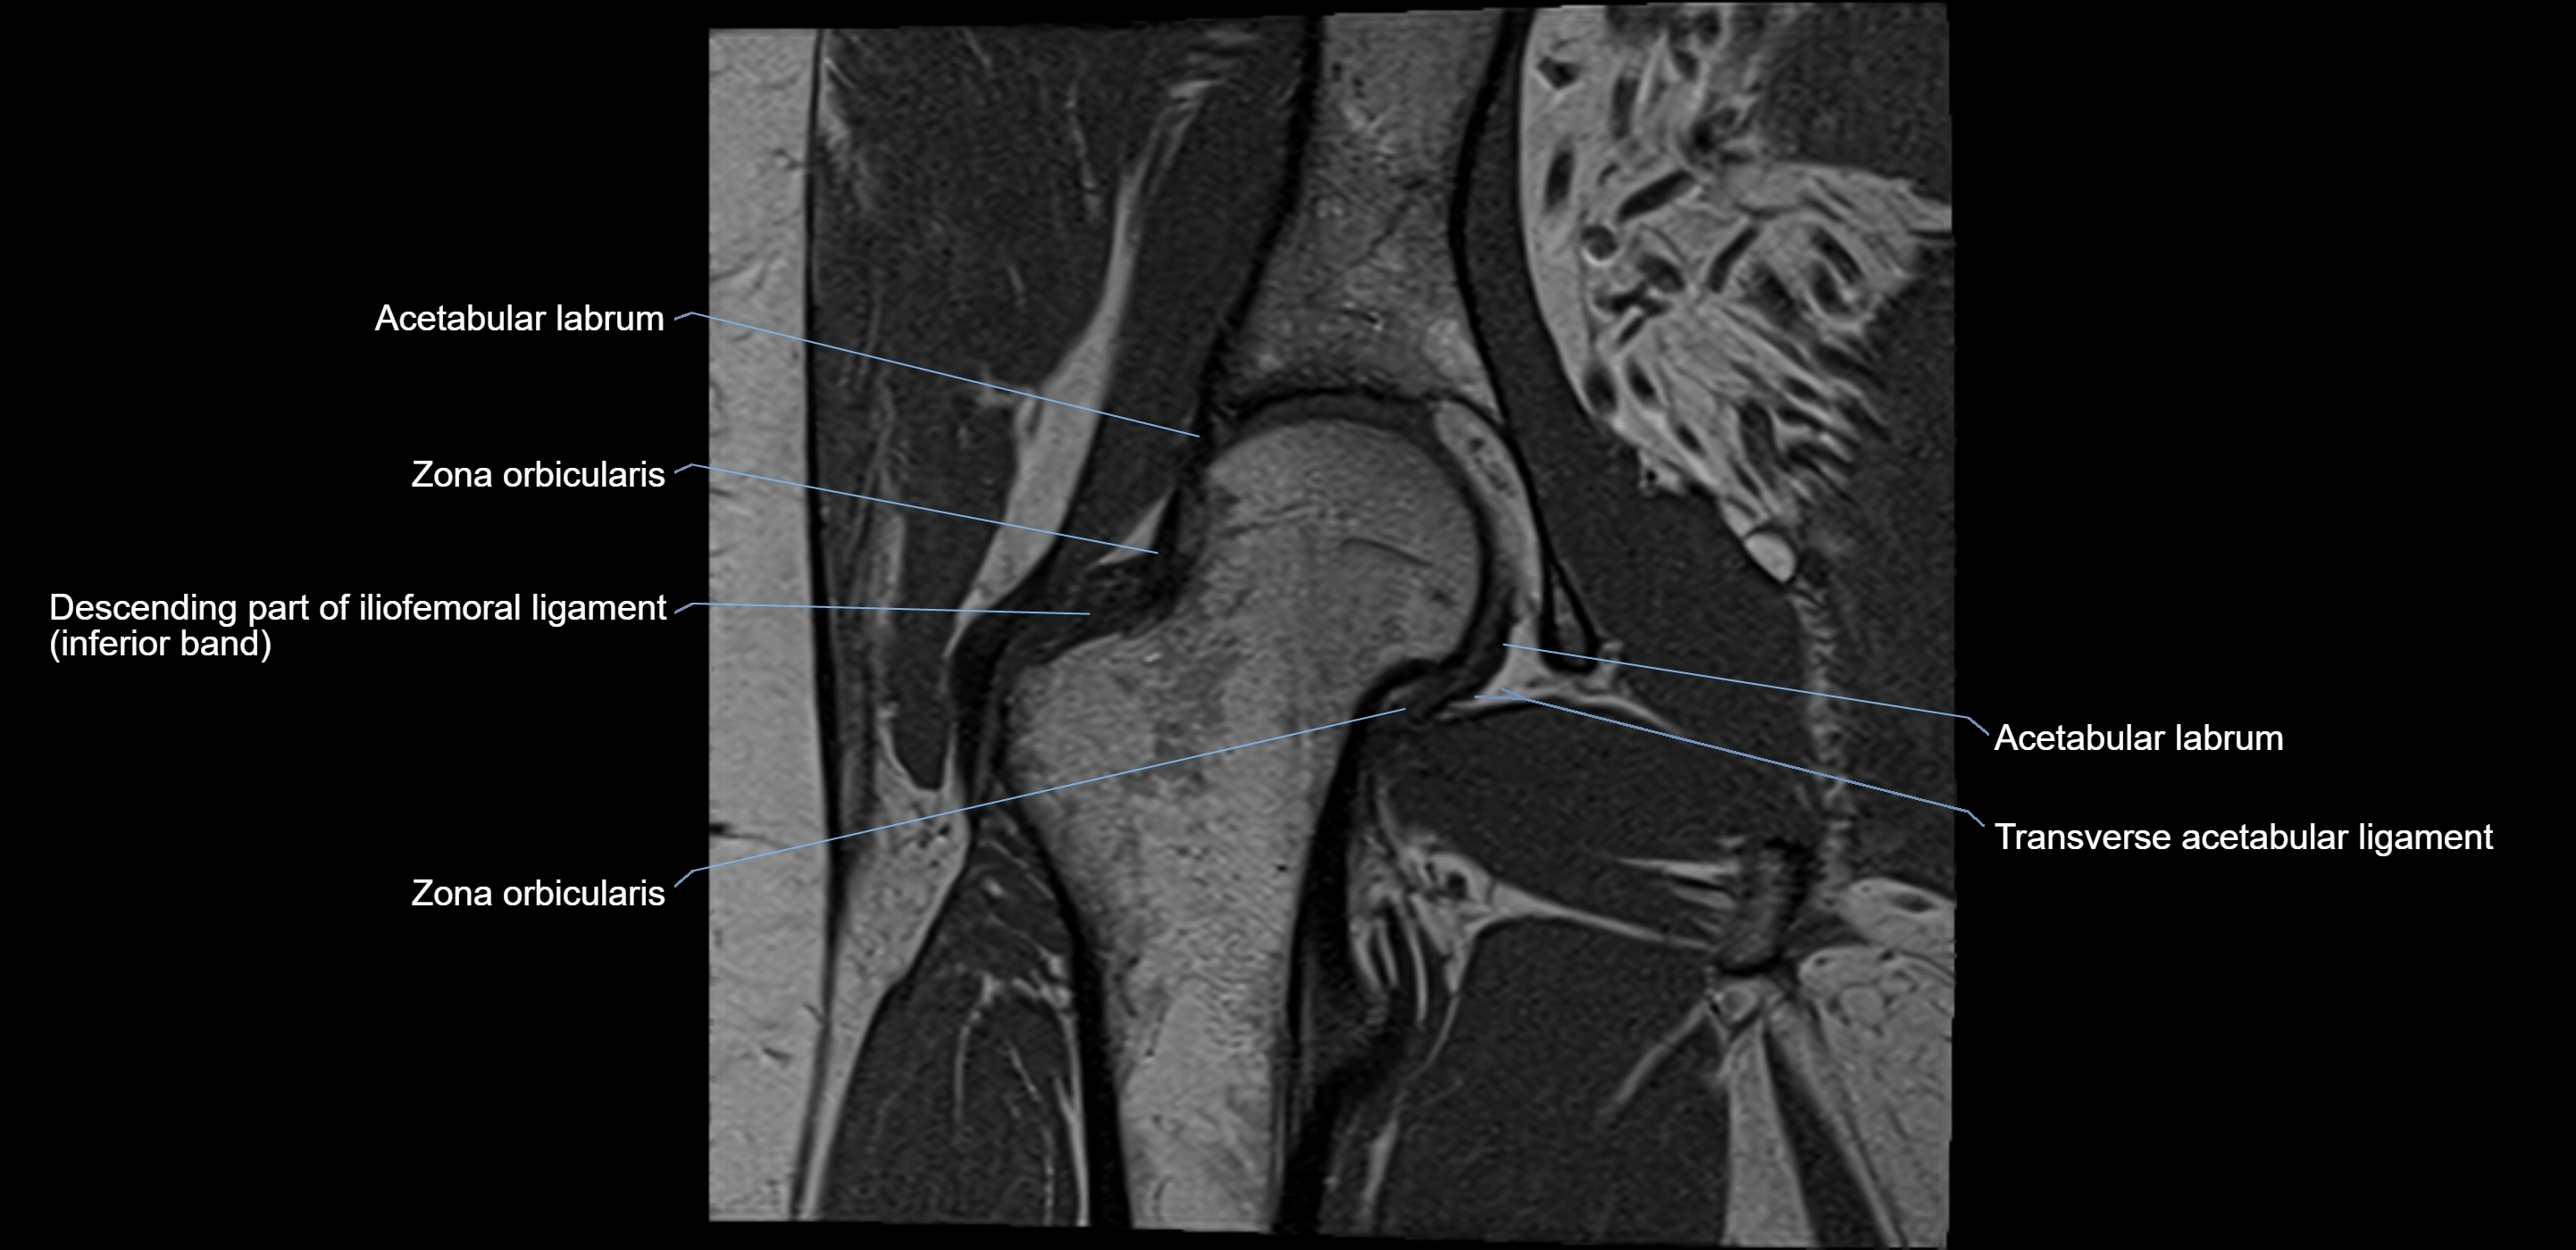

MRI Appearance

T1-weighted images:

• Labrum: low signal intensity (dark)

• Surrounded by intermediate signal joint fluid (bright on arthrogram)

• Tears: linear or focal areas of intermediate-to-high signal interrupting labral continuity

T2-weighted images:

• Joint fluid: bright, making labral tears visible as fluid extending into or around labrum

• Degeneration: may show areas of increased signal within labrum

MRI image

image